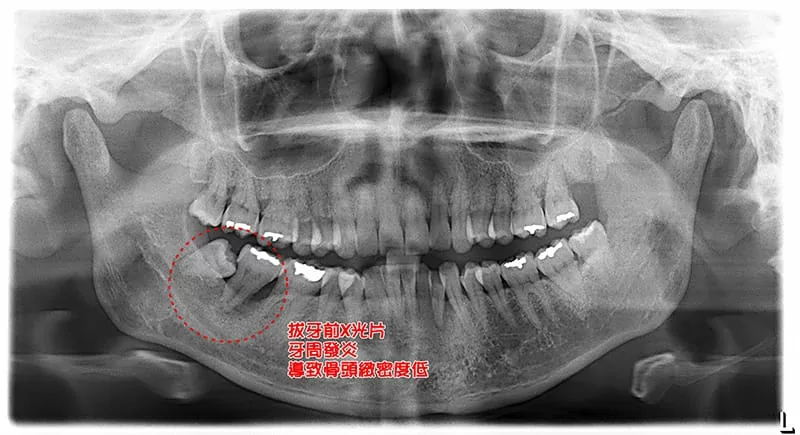

拔牙填補骨膠原蛋白,骨質增生超神奇

經由X光片顯示,患者右下的第二大臼齒及第三大臼齒有一區黑影,董建華醫師透過3D電腦斷層,確定患者該區因牙周發炎導致骨頭嚴重流失,牙齒無法正常的咬合,判斷需拔牙,並因為骨頭破壞程度較大的關係,希望日後有足夠垂直向、橫向骨頭,來做人工牙根,所以建議患者可以補骨膠原蛋白,促進傷口癒合及骨質增生。

( 治療前 )

( 治療前:X光片上呈顯黑色暗影 )